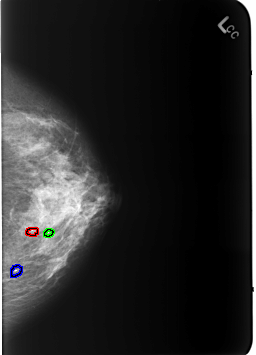

B_3235_1.LEFT_CC

FILE: B_3235_1.LEFT_CC.OVERLAY

TOTAL_ABNORMALITIES 3

ABNORMALITY 1

LESION_TYPE CALCIFICATION TYPE ROUND_AND_REGULAR-LUCENT_CENTER DISTRIBUTION N/A

ASSESSMENT 2

SUBTLETY 5

PATHOLOGY BENIGN_WITHOUT_CALLBACK

ABNORMALITY 2

ABNORMALITY 3